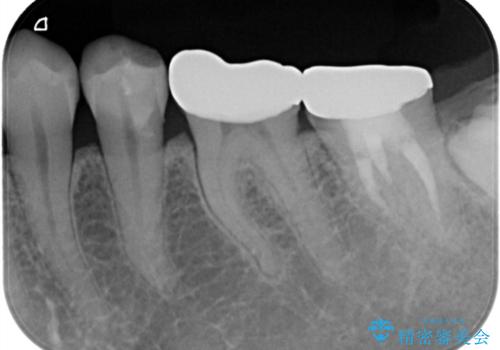

- 他院で、仮歯にしたがセラミックの値段が高すぎると思ったため治療相談も含めて来院された患者様です。

仮歯を新調させていただき、再度虫歯治療を行なって、歯の形を作りセラミックを入れさせていただきました。

フルジルコニアクラウン 7万円(税抜)

仮歯 1万円